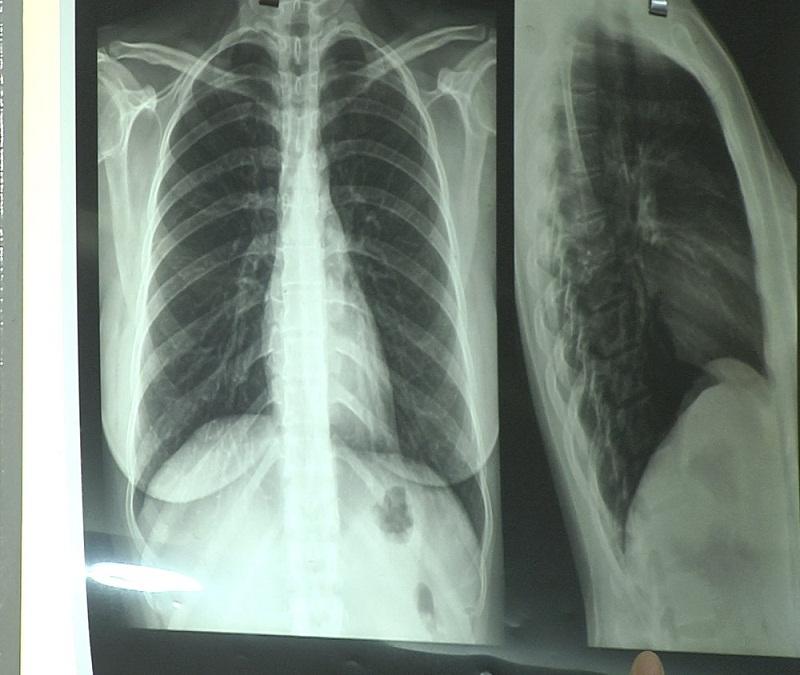

Os sintomas iniciais são febre baixa, cansaço, mal estar, fraqueza, tosse, dor no corpo, suor noturno e falta de apetite. Ao longo do tempo, o mal estar se acentua, o paciente emagrece e a tosse persiste, podendo ocorrer com sangue. A doença também pode atingir outros órgãos. O diagnóstico é feito com raio-X e exames de escarro.